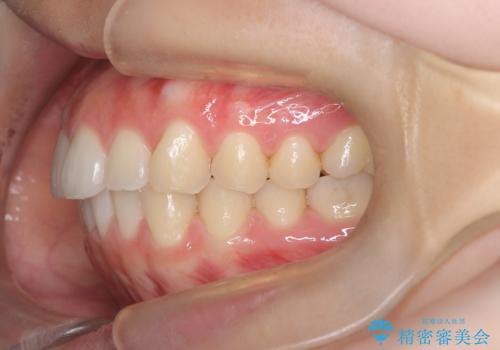

下顎前歯の叢生を短期間で改善

- 患者様は、下顎前歯のガタガタ(叢生)の改善を希望して来院されました。診断の結果、非抜歯で治療可能であると判断し、透明で目立たないインビザラインを使用する矯正治療計画を立案しました。短期間での治療を希望されていたため、IPR(歯間削合)を併用してスペースを確保しながら、効率的に歯を並べることを目指しました。

治療では、インビザラインを用いて計画的に歯を移動させ、短期間での歯列改善を実現しました。IPRを行うことで、抜歯をせずに必要なスペースを確保し、歯列全体を整えました。治療中は、装置の適切な装着時間を守ることが重要であり、患者様にも継続的な協力をお願いしました。また、歯肉や歯根への負担を最小限に抑えるため、歯の移動を慎重に管理しました。結果として、短期間で下顎前歯の叢生を改善し、自然な見た目と機能性を兼ね備えた歯列を実現できました。